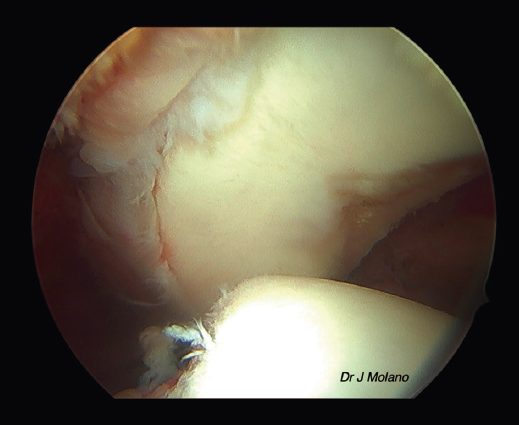

Figura 2. Visión artroscópica desde el portal superior de un hombro derecho con lesión Hill-Sachs off track; defecto glenoideo del 20%.